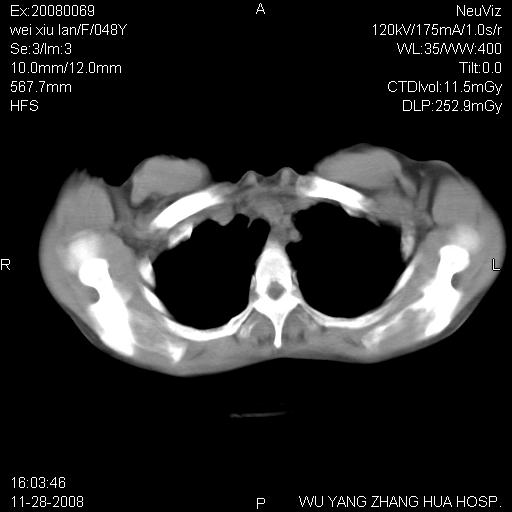

标题: CT16847:女,48岁,咳嗽,发热两日,平常偶有上腹部不适。 [打印本页]

标题: CT16847:女,48岁,咳嗽,发热两日,平常偶有上腹部不适。

左下肺不张、膈膨升,胸腔胃

1.左侧隔膨升

2.左下肺炎性改变

胃、脾脏及部分肠管明显升高,并压迫心脏移位,

首先考虑:左侧膈疝。

左侧胸腔内见胃肠及脾脏影

支持膈疝